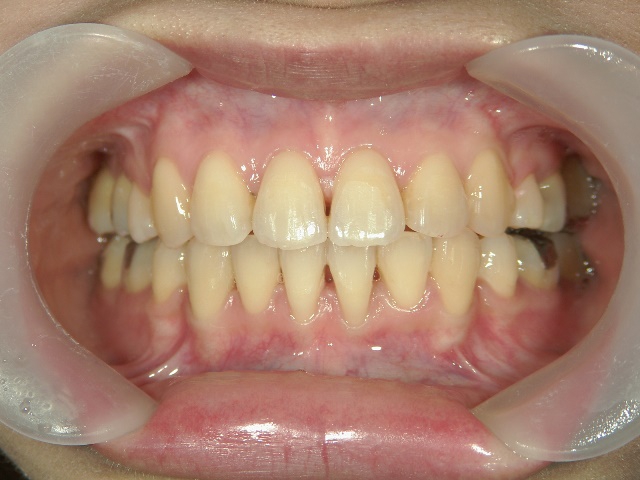

矯正歯科(全顎ワイヤー矯正)治療後

矯正歯科 治療後